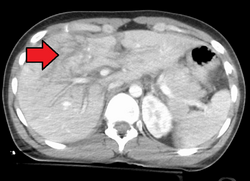

Imaging, such as the use of ultrasound or a computed tomography scan, is the generally preferred way of diagnosis as it is more accurate and is sensitive to bleeding, however; due to logistics this is not always possible.[6] For a person who is hemodynamically unstable a focused assessment with sonography for trauma (FAST) scan may take place which is used to find free floating fluid in the right upper quadrant and left lower quadrant of the abdomen. The FAST scan however may not be indicated in those who are obese and those with subcutaneous emphysema.[7] Its speed and sensitivity to injuries resulting in 400mL of free-floating fluid make it a valuable tool in the evaluation of unstable persons. Computed tomography is another diagnostic study which can be performed, but typically is only used in those who are hemodynamically stable.[7] A physical examination may be used but is typically inaccurate in blunt trauma, unlike in penetrating trauma where the trajectory the projectile took can be followed digitally.[8] A diagnostic peritoneal lavage (DPL) may also be utilized but has limited application as it is hard to determine the origin of the bleeding.[9] A diagnostic peritoneal lavage is generally discouraged when FAST is available as it is invasive and non-specific.[7]